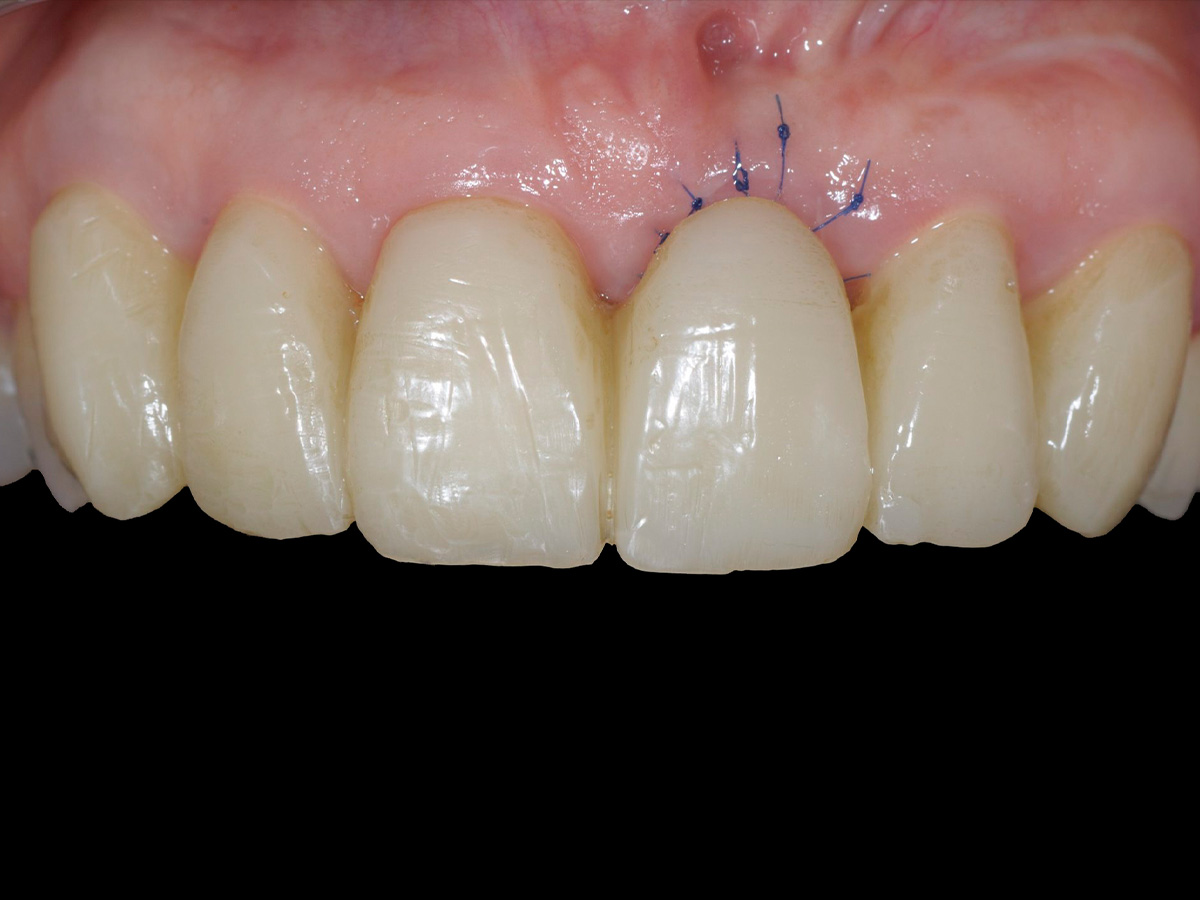

Abbildung 2

Klinische Ausgangssituation.